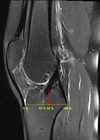

An 18-year-old man sustains a twisting injury to the left knee while playing football. An MRI scan is shown in Figure 48. What is the most likely diagnosis?

lateral mensicus tear

MRI scan shows a displaced, bucket-handle lateral meniscus tear. The sagittal view shows the typical “large anterior horn” sign, or “double meniscus” sign in which the displaced bucket-handle fragment appears just anterior to the native anterior horn of the lateral meniscus. The presence of the fibula on the sagittal view confirms this as the lateral compartment. The image is lateral and the cruciate ligaments are not visualized. The articular cartilage shown does not demonstrate an osteochondral lesion.